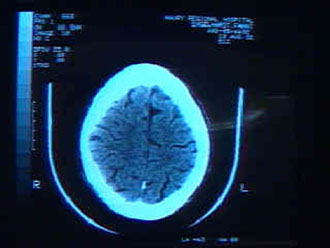

Αμερικανοί επιστήμονες πέτυχαν να μειώσουν την συσσώρεση πλακών β-αμυλοειδούς, χαρακτηριστικό της νόσου Αλτσχάιμερ, από τον εγκέφαλο γενετικά τροποποιημένων ποντικιών, σύμφωνα με στοιχεία που δημοσιεύονται στο επιστημονικό έντυπο Journal of Clinical Investigation.